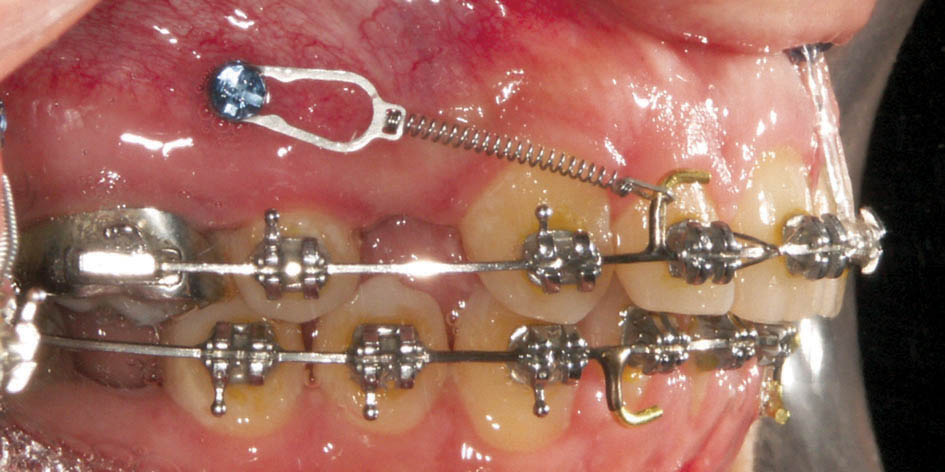

اگر قرار است خلفیها اصلاً جلو نیایند باید مینی اسکرو بگذارید (شکل 24-3) بدین صورت فضای بدست آمده از کشیدن پرمولر خرج دیستاله شدن قدامیها میشود. اگر بیمار در فک بالا دچار کرادینگ شدید باشد و اورجت زیادی نداشته باشد، مصرف فضای پرمولر اثری روی نیمرخ صورت ندارد، اما اگر در فک بالا کرادینگ نداشته باشد و اورجت زیاد باشد آن موقع با عقب رفتن قدامیها شاهد تو افتادن لب بالا خواهیم بود (شکل 25-3 و 26-3)

شکل 24-3: بیمار با اکلوژن یک کاسپ کامل کلاسII و پروتروژن. اعمال تمام نیروها به مینی اسکرو بعد از کشیدن پرمولر اول.

Laceback را به مینی اسکرو بزنید تا مانع پروترود شدن کانین بشود. هیچ وقت Bendback نزنید تا انسیزورها سریع پروترود بشوند و مرتب گردند. بعد از مرتب شدن انسیزورها سیم را ضخیم نمایید (0.016 حرارتی و0.019x0.025 حرارتی و 0.019x0.025 استیل). در زمان سیم استیل، Passive Tieback را به مینی اسکرو بزنید و ماه بعد برای بستن فضا حتماً از فنرهای نیتی eyeletدار استفاده کنید تا نیروی ملایم و ممتد اعمال کند و باعث لقی مینی اسکرو نشود.